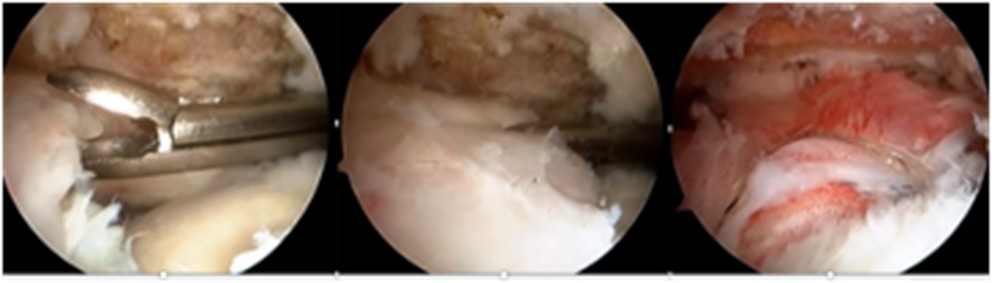

前十字靭帯損傷・半月板損傷

前十字靭帯(ACL)とは膝関節の中央にある靭帯で、大腿骨(太ももの骨)と脛骨(すねの骨)をつないでいます。膝の前後の動きやねじれに対する安定性を保つ役割があります。

前十字靭帯損傷の主な原因は急な方向転換やストップ動作(サッカー、バスケ、ラグビーなど)、ジャンプ後の着地での膝のねじれ、接触プレー(他選手との衝突など)です。症状としては「ブチッ」という音や感覚、膝の激しい痛みと腫れ(数時間以内に顕著になる)、膝の不安定感(膝が「抜ける」ような感覚)、可動域の制限です。問診と身体診察(ラックマンテストなど)、MRI(断裂の有無や程度の評価)、超音波検査やX線(他の損傷との鑑別)で診断をします。治療法としては、スポーツ復帰や将来的な関節症性変化のリスクから基本的に手術治療が選択されます。

手術は自家腱(ハムストリングス腱、BTBなど)を使って再建するのが一般的です(図2・3)。手術後は6か月〜1年程度のリハビリが必要となり、膝周囲筋の強化、可動域の回復、神経筋コントロールの再学習、再受傷を防ぐための予防トレーニングも重要となります。半月板損傷、軟骨損傷を伴うことがあり、同時に手術治療を行うことがあります(図4)。